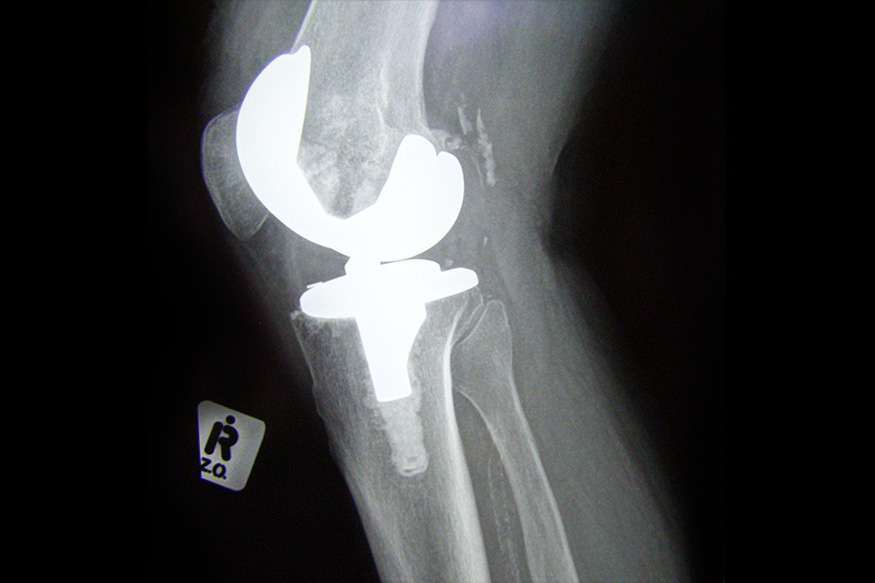

Knee Arthroplasty

There are insufficient data on the geographic variation and disparities in the use of elective primary total hip and knee arthroplasty for Medicare beneficiaries. The goals of this study by Thirukumaran et al were to identify these variations and disparities, determine whether Black Medicare beneficiaries have continued to undergo lower numbers of total hip and total knee replacements across regions and whether these disparities affected all Black beneficiaries or preferentially affected socioeconomically disadvantaged Black beneficiaries.